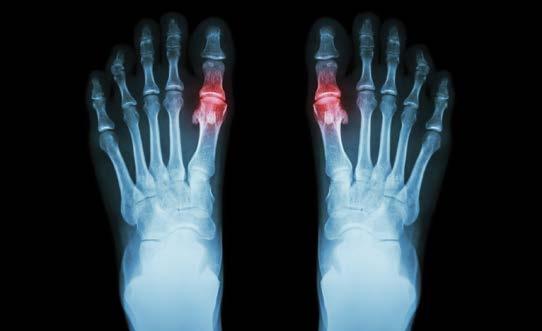

Gota es una condición caracterizada por la deposición de cristales de urato monosódico monohidratado en las coyunturas, produciendo inflamación y dolor severo. Esta condición es una comorbilidad común en pacientes con fallo cardíaco (HF), donde estudios han encontrado que la prevalencia de gota en estos pacientes es de 1640%. Entre los agentes terapéuticos que se utilizan para el manejo de la gota se encuentran la colchicina, los corticosteroides y los antiinflamatorios no esteroidales (NSAIDs, por sus siglas en inglés). Ahora, el fallo cardíaco es una condición que resulta de la inhabilidad del corazón de contraerse efectivamente para bombear la sangre a través del cuerpo. Dada la patofisiología de esta condición, agentes como los esteroides y NSAIDS se tratan de evitar, ya que podrían exacerbar el fallo por su efecto en la retención de fluidos corporales. Por esto, se limita la selección de posibles agentes terapéuticos en el manejo de

gota en pacientes con fallo cardiaco descompensado.